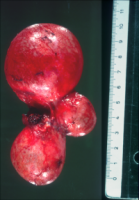

Bei einer 16-jährigen Jugendlichen wurde wegen Flankenschmerzen und sonographischem Verdacht auf einen linksseitigen zystischen Nierentumor die Freilegung durchgeführt (Abbildung 3). Dabei fand sich ein zystischer Tumor (Abbildung 4). Die histologische Untersuchung ergab eine multizystische, dysplastische Nierendegeneration.

Da die unilaterale multizystische Nierendysplasie nicht immer vergrößert ist, fallen derartige Tumoren unter Umständen erst im Erwachsenenalter anlässlich Untersuchungen aufgrund anderer Erkrankungen auf. Die Organe werden zumeist wegen der Differentialdiagnose zum zystischen Nierenzellkarzinom entfernt.